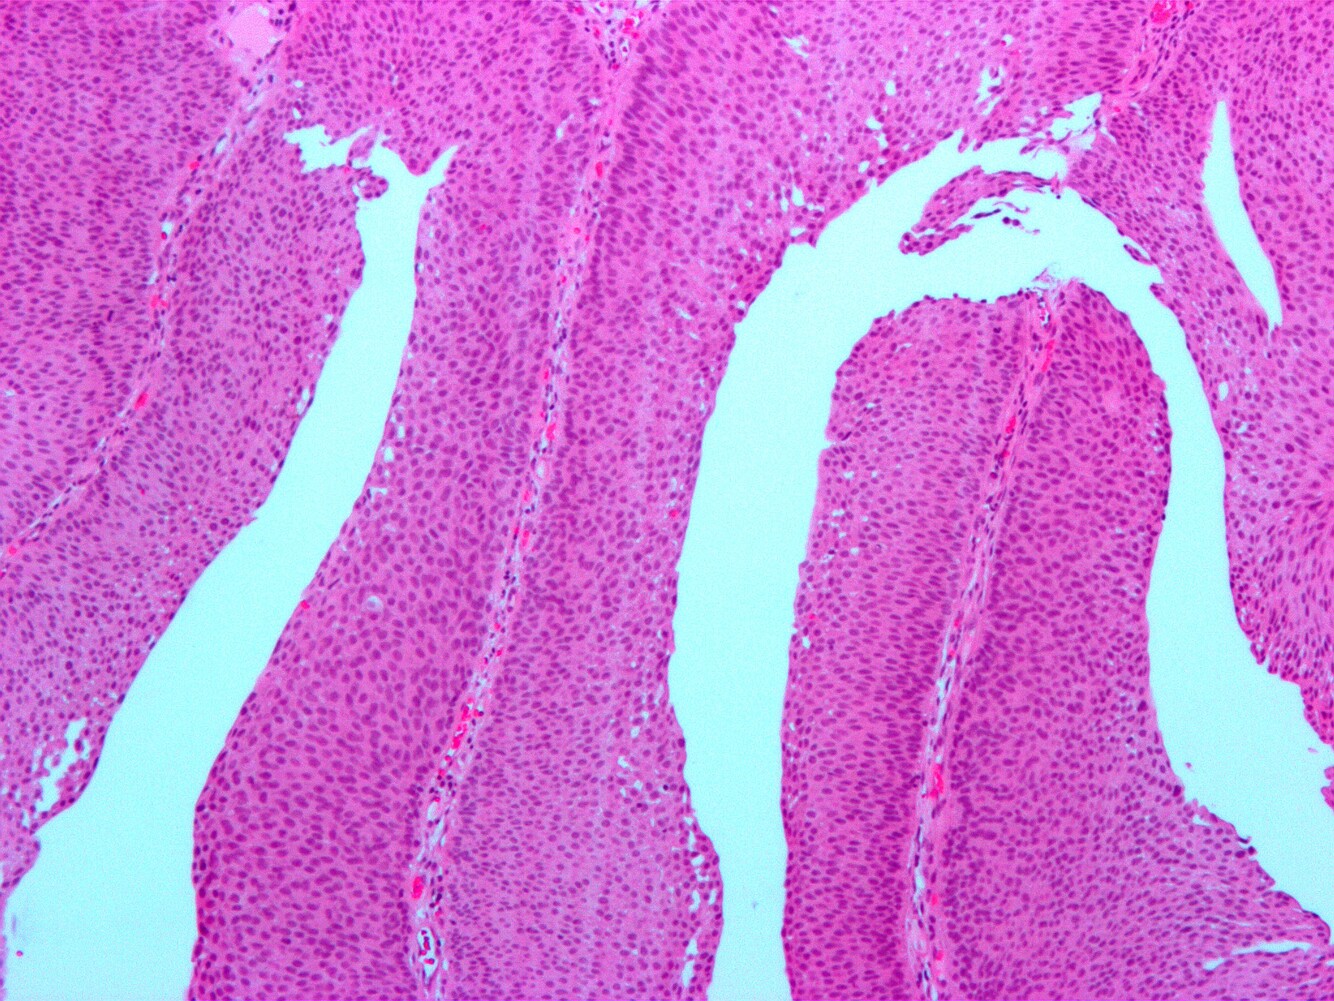

Urothelial Proliferaiton of Uncertain Malignant Potential (U-PUMP)

Markedly thickened urothelium (> 10 cells).

No or minimal atypia, but increased cell density. Unlike papillary lesions, there are no true papillary fronds with fibrovascular

cores. Instead, there are just undulating mucosal folds.

This is a clonal neoplasm, and may be early pre-cursor to low grade papillary urothelial carcinoma (often at the “shoulder” of these lesions).

Followed clinically.